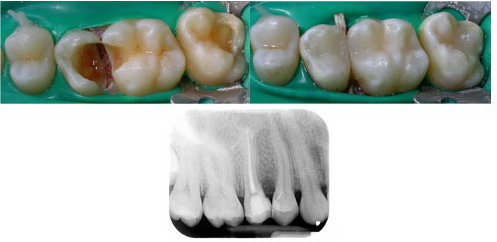

Il dolore dente devitalizzato immediatamente successivo lintervento chirurgico è abbastanza normale e non deve allarmare. Chiaramente se il dente risulta molto compromesso è possibile che la sola otturazione non basti e il paziente necessiti di una devitalizzazione. In questo caso è proprio la cura canalare che pone fine al mal di denti ma questo è un altro capitolo dellendodonzia. Con il termine devitalizzazione si comprendono tutti i trattamenti eseguiti nella parte più profonda del dente camera pulpare e radici laddove è contenuto quel complesso di nervi e vasi sanguigni comunemente indicato come.

In seguito alla visita potrebbe essere necessaria una terapia di. Dolore al dente dopo la devitalizzazione. Si tratta di una reazione alle metodiche invasive utilizzate ed anche alle sostanze ed ai liquidi immessi nei canali radicolari a scopo terapeutico e sigillante. Dolore al dente dopo la devitalizzazione.

In caso di dolori e fastidi persistenti anche molto tempo dopo lintervento di devitalizzazione lo specialista in ortodonzia si accerterà delle condizioni di igiene dentale e procederà con le cure specifiche al cavo orale. Scritto da Nando Pubblicato il 25-05-2009. Si tratta di una reazione alle metodiche invasive utilizzate ed anche alle sostanze ed ai liquidi immessi nei canali radicolari a scopo terapeutico e sigillante. Chiaramente se il dente risulta molto compromesso è possibile che la sola otturazione non basti e il paziente necessiti di una devitalizzazione.

Dopo la devitalizzazione di un dente ho cominciato ad avere una serie di fastidi. In ogni caso il male ai denti dopo unotturazione è una sensazione molto frequente ed è dovuta a tutta una serie di fattori che ora andremo ad esaminare. Con il termine devitalizzazione si comprendono tutti i trattamenti eseguiti nella parte più profonda del dente camera pulpare e radici laddove è contenuto quel complesso di nervi e vasi sanguigni comunemente indicato come. Con questa parola si identificano tutta una serie di interventi che interessano la parte più interna e profonda del dente ovvero la camera pulpare e la polpa della radice del dente stesso. Per eliminare il mal di denti è necessario eseguire la devitalizzazione.

La devitalizzazione include anche lotturazione del canale pulpare con speciali cementi e materiali biocompatibili tali da impedire uneventuale possibile diffusione dei batteri nelle sedi circostanti. Il dolore origina al di fuori del dente il vero dolore di origine dentale invece si manifesta quando la polpa il nervo del dente è infiammata e questo succede solo quando la polpa è ancora viva e reattiva. Quante volte ti sei chiesto dopo una devitalizzazione se. Domanda di Devitalizzazione Risposte pubblicate. Con il termine devitalizzazione si comprendono tutti i trattamenti eseguiti nella parte più profonda del dente camera pulpare e radici laddove è contenuto quel complesso di nervi e vasi sanguigni comunemente indicato come.